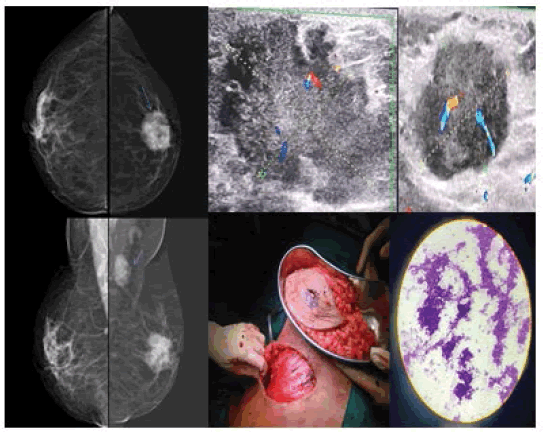

10. Case 11: Duct cell carcinoma: 55-year-old female came with a lump in her left breast (Figure 15).

Figure 15. DM: Breast composition-Cat B. Left breast showing irregular large micro lobulated dense mass lesion in the retro areolar region associated with architectural distortion, adjacent skin thickening, nipple retraction, and significantly enlarged left axillary lymph nodes. USG showing irregular large lobulated solid hypoechoic lesion with central vascularity on Doppler and enlarged left axillary lymph nodes of same morphology. BI-RADS 5 Histopathology-DCC

11. Case 12: Mucinous Carcinoma: 59-year-old female came with a lump in her left breast (Figure 16).

Figure 16. Digital Mammography (DM): Breast composition-cat B. Left breast showing an irregular dense mass lesion with indistinct margins noted in the upper inner quadrant in anterior portion with significant B/L axillary lymph nodes largest seen in the right axilla. USG: showing small relatively well-defined lobulated hypo to an isoechoic mass lesion in the left breast with well-defined enlarged hypoechoic largest lymph node in right axilla-BI-RADS 5. Histopathology- Mucinous